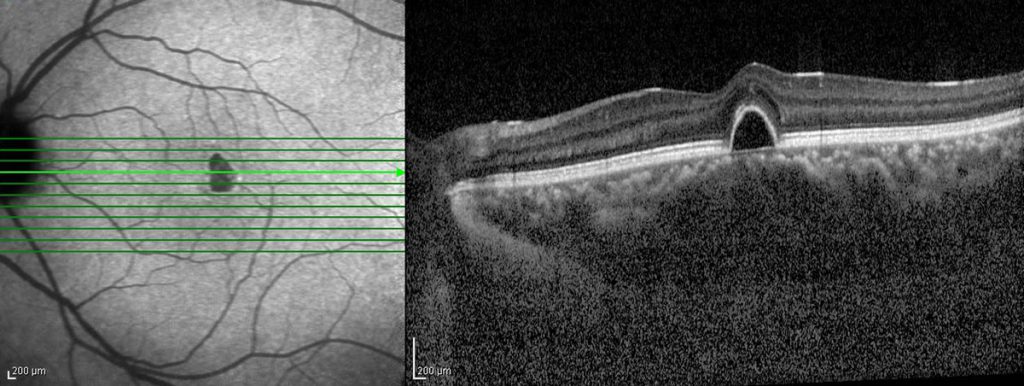

Aquesta degeneració pot presentar-se de diferents maneres:

- DMAE Seca: actualment no existeix cap tractament efectiu.

- DMEA humida: els tractaments que existeixen són intravitris (punció intravitrea indolora amb anestèsia tòpica). Es realitzen sempre en quiròfan o àmbits estèrils i són tractaments ambulatoris.